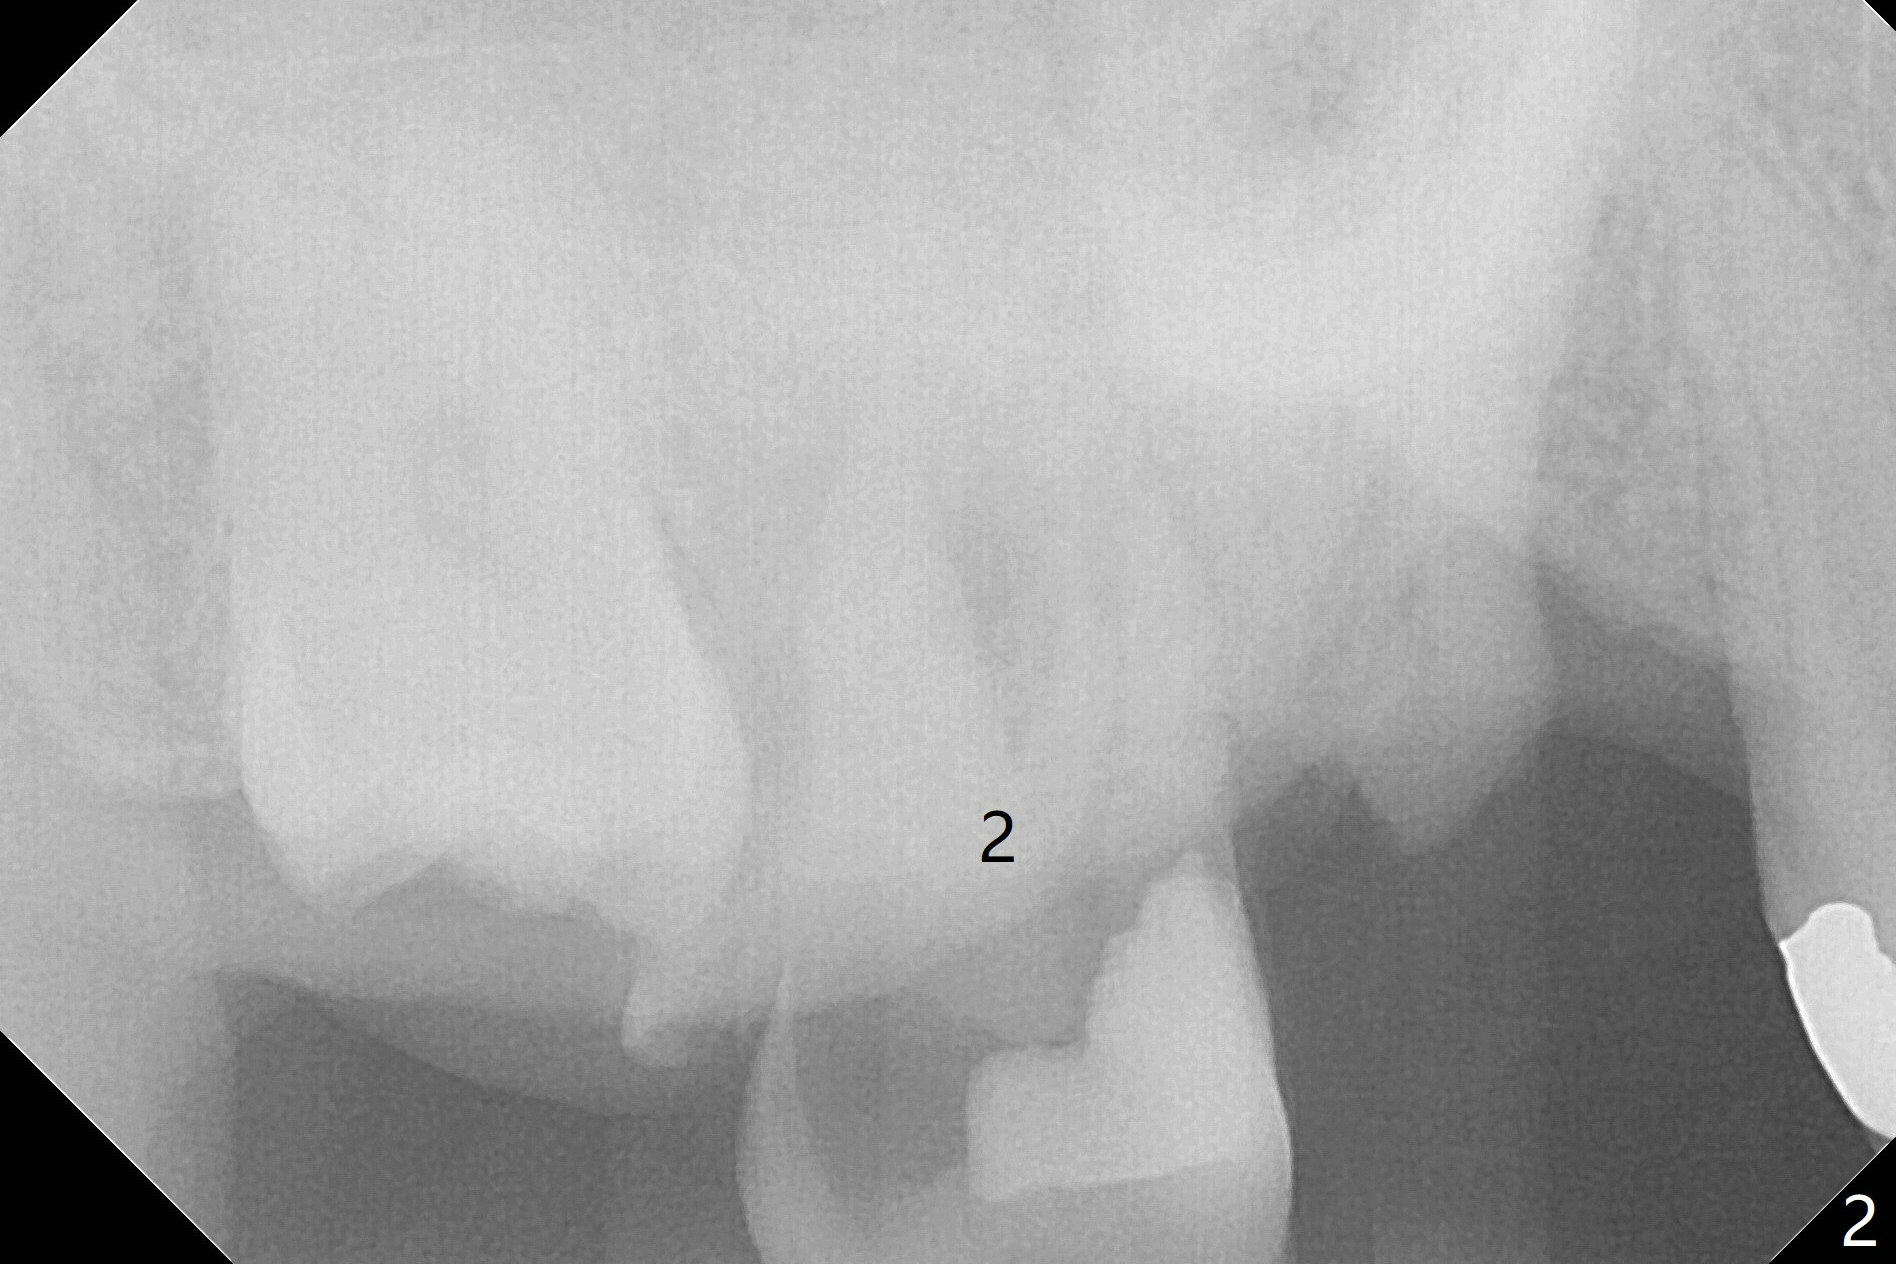

A 58-year-old man had 2 missing molar 3 years ago (Fig.1). Later the tooth #2 fractures with apparently severe bone loss (Fig.2). If the septum is lost, bone height is around 3 mm (Fig.3). Take PA before using Magic Sinus Lifter. Since his bone density is high, increase exposure time. If the septum is present (Fig.4), use Magic Drills sequentially (1.6, 2.8, 3.2 mm ....). PRF plug and membrane (1 each) are to be prepared.